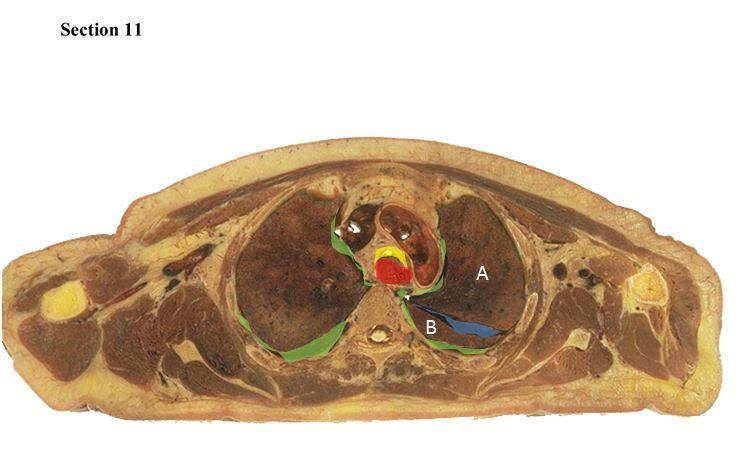

11

The blue space is the _____ and it separates structure A which is the _____ of the lung from structure B which is the _____ of the lung.

A

oblique fissure

superior lobe

inferior lobe